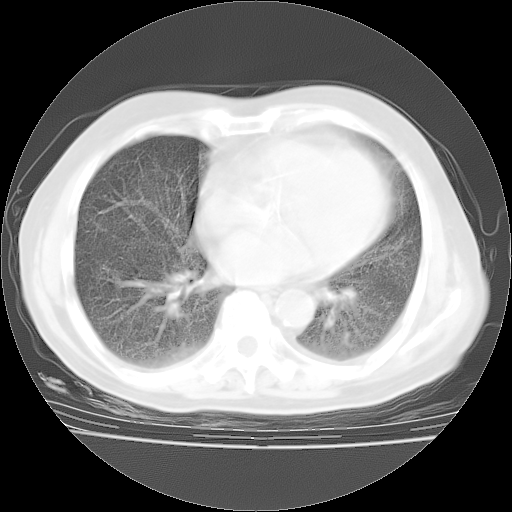

4月28日肺部CT——再次出现类似去年5月9日——透光度降低,(影像科认为)“间质性”改变。

4月28日肺部CT——再次出现类似去年5月9日——透光度降低,“间质性”改变。